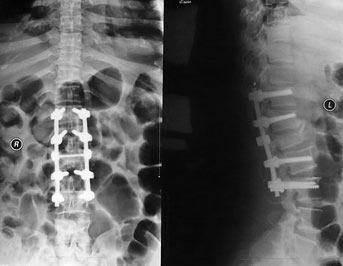

2、一般骨骼系统摄影都要采取正侧两个摄影位置,一般不会只照一个位置,有些特殊部位还要加斜位、轴位、切线位。

(图片来自网络

3、骨骼系统摄影范围应该包含周围的软组织;四肢骨摄影应该包含邻近的骨关节;脊柱摄影要包含邻近的部位(比如腰肢摄影时,包含部分胸椎,便于腰椎的定位、计数)。